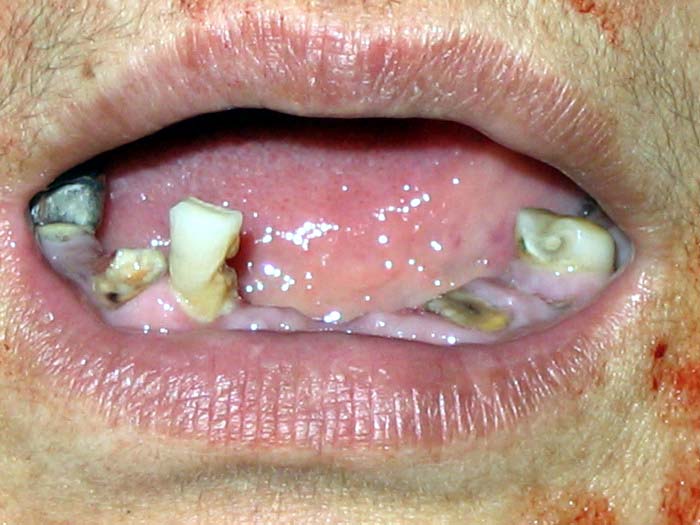

Published on 10/18/2004 		我因说真话而遭沈阳市看守所、龙山、马三家的迫害---牙齿被撬碎